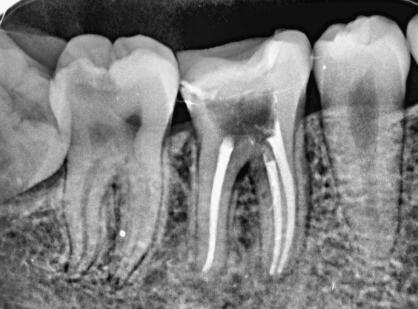

根管治疗通常分为4个步骤,分别是术前准备、牙髓打开、根管充填。术前准备主要包含将牙齿当中陈旧填充物或者腐烂填充物去除,牙髓打开以后,充分暴露出牙髓组织,把牙腔内牙髓组织深层清除,然后采用特殊仪器塑造根管,采用药物对根管做消毒,把根管紧密填充,并且做冠状面修复,进而达到控制牙齿感染,修复牙齿缺损情况,能够使根尖周病变快速愈合,还能够防止根尖周病变复发。做根管治疗通常用于治疗根尖周病和牙髓疾病,要选择技术手法较专业的医生进行治疗。